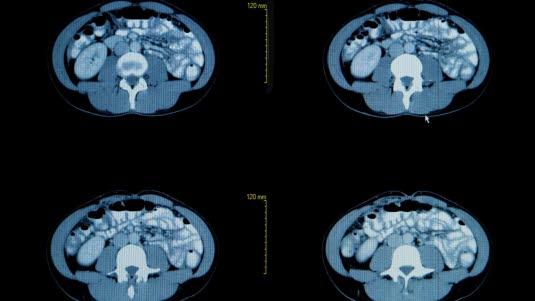

Normale lunger og bronkierCT er en forkortelse for Computed Tomography. CT bilder dannes av samme type røntgen-stråler som ved vanlig røntgen. CT teknikken skiller seg fra røntgen ved at man benytter en mer avansert metode for bestråling og registrering av strålene, og en datamaskin brukes for å sette dataene sammen til et bilde som dekker tre dimensjoner, ikke bare to. Røntgenkilden og de delene som fanger opp strålene, røntgen-mottakerne eller detektorene, beveger seg rundt området som avbildes, og muliggjør framstilling i tverrsnitt og tre dimensjoner. Fordelen med denne metoden er at den kan påvise svært små forandringer og at den i større grad kan skille mellom ulike typer bløtvev (ikke beinvev - f.eks. organer).

CT-bilder er svarthvite. Organene fremstilles i ulike grader av grått. Vev med lav tetthet, f.eks. luftfylte hulrom, vises som mørke eller svarte partier. Vev med høyere tetthet vises i lysere gråtoner. Jo høyere tetthet, jo lysere. Beinvev fremstilles hvitt.

Siden CT kan skille mellom ulike indre organ, såkalte bløtdeler, så kan CT av brysthulen (thorax) gi detaljerte tverrsnittsbilder og tredimensjonale bilder av lungene, bronkiene (luftrørene), lungehinnen (pleura), strukturer i midtre del av brysthulen (mediastinum) og hjertet. Bildene fremstår i ulike nyanser av grått. Jo lysere skygge, jo høyere tetthet har vevet eller strukturen. Bildekvaliteten kan forbedres ved samtidig bruk av kontrastinjeksjon.